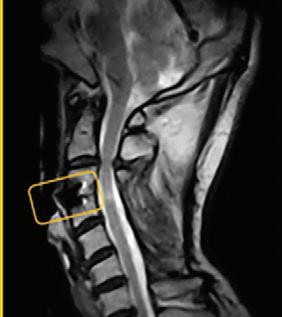

What a weight-bearing MRI reveals vs. a Supine MRI

G-scan Brio Reveals What Supine MRI Misses

Conventional MRI may not demonstrate the pathology related to these symptoms, but G-scan Brio gives you a new point of view so you can accurately diagnose MSK pathologies affected by weight-bearing position.

The G-scan Bro is superior to other MRIs because both the magnet and patient can rotate from 0 to 90 degrees.

G-scan Brio offers a revolutionary MRI approach that increases diagnostic accuracy and confidence for musculoskeletal applications.